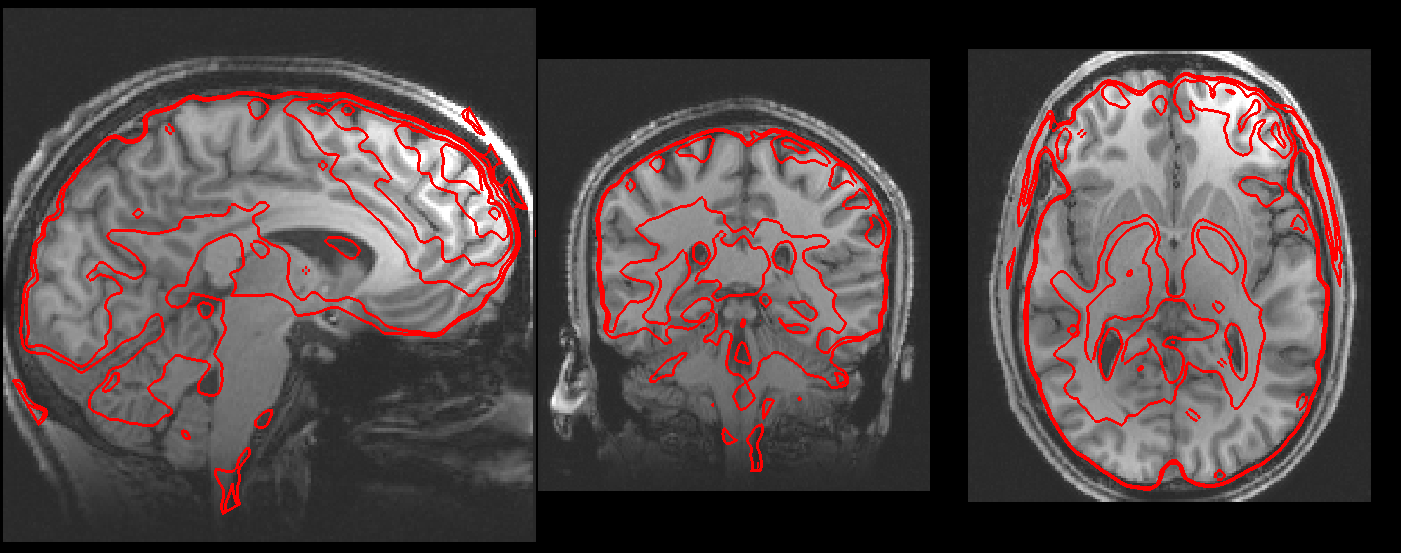

The Registration page displays a summary of the fMRI → structural, and structural → standard template registration stages. In a real fMRI analysis it is very important to manually check that the registration was successful.

- Summary registration, FMRI to standard space: This image shows the fMRI image in the background in grey, and an outline of the standard template overlaid on it in red - this allows you to assess the overall results of both registration stages.

- Registration of example_func to highres: This image has two rows, both showing the fMRI (example_func) to structural (highres) registration. The first row shows the fMRI image in the background in grey and an outline of the structural image overlaid in red. The second row shows the structural image in the background in grey, and the fMRI image outline overlaid in red.

- Registration of highres to standard: This image shows the same information as above, but for the structural to standard template registration.

- Registration of example_func to standard: This image shows the same information as the Summary registration, but in more detail.